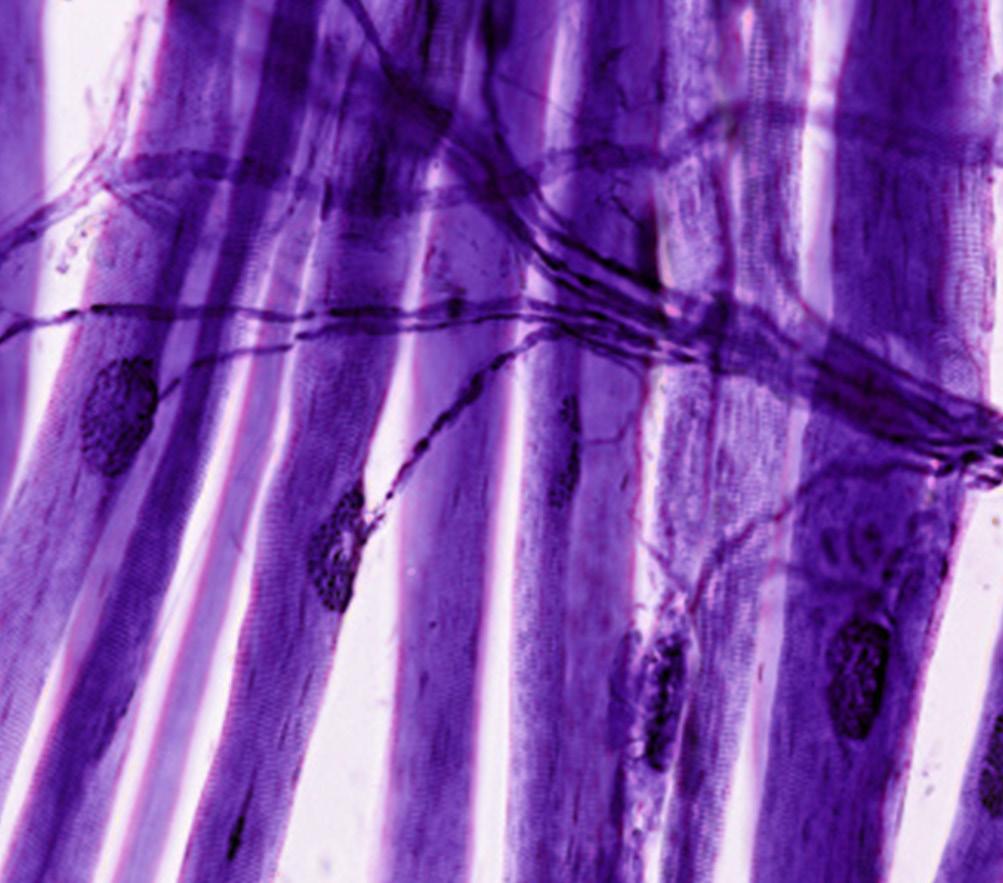

The study of neurodegenerative diseases has evolved from describing manifestations of abnormal brain function and neuropathology to understanding molecular mechanisms. Today, it is well known that many seemingly disparate neurodegenerative disorders share a common etiology based in abnormal protein folding.

The Diamond Lab studies neurodegeneration from the standpoint of prion biology and protein aggregation. His ideas and the tools that have been developed in his lab have helped transform the scientific community’s understanding of how neurogenerative diseases progress.

“All major neurodegenerative diseases are relentlessly progressive, and virtually all are linked to the accumulation of protein amyloids,” Dr. Diamond

says. “My lab focuses primarily on the tau protein, whose aggregation underlies neurodegeneration.”

Like the prion protein, tau adopts many distinct pathological conformations that replicate within cells and underlie different tauopathies, Dr. Diamond explains. In recent years, he and his team have uncovered how abnormal assemblies of the tau protein move between cells and serve as templates for their own replication.

The researchers traced this conformational change to a key component of the tau protein, proposing that a type of “hairpin” structure hides an amyloidogenic sequence in the inert monomer, whereas in the seed-competent monomer the tau “unfolds” locally to expose the amyloidogenic sequence so the protein can subsequently aggregate.

Most recently, the duo followed up these findings with a report describing how the tau monomer converting from the “inert” form to “seed-competent” form represents the first detectable step in the initiation of tauopathy. They are now using computational approaches coupled with experimental molecular genetics to decipher how tau folds to form pathological aggregates and what cellular factors might trigger this process.

“We are beginning to understand how a single tau monomer changes shape to form a pathological monomer and then a pathological aggregate,” Dr. Joachimiak explains. “A better knowledge of this process may contribute to the design of interventions that target diseasespecific tau conformations.”